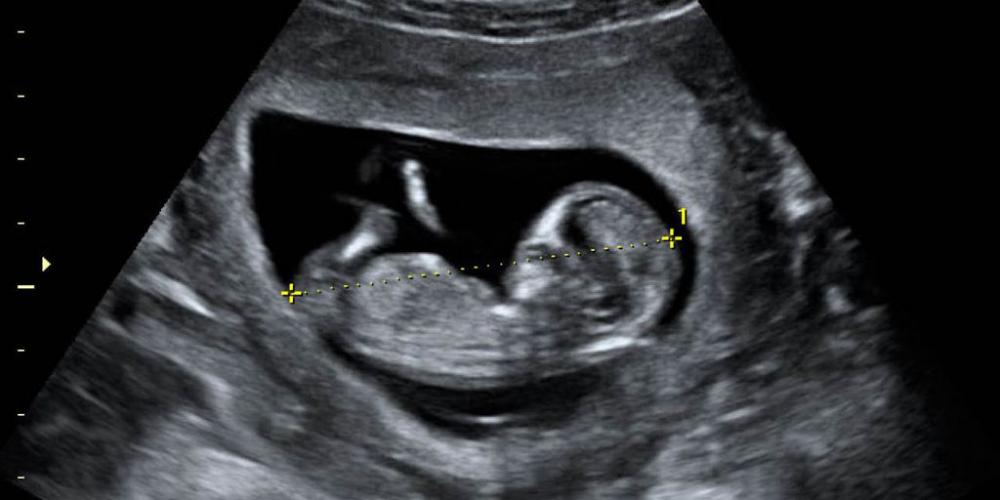

24 NIÑOS POR DÍA SON ELIMINADOS EN LA CIUDAD DE BUENOS AIRES

Gracias al buen trabajo de Notivida se conocen datos respecto de la eliminación de niños mediante el aborto en el sistema de salud porteño durante el primer año de la siniestra ley Nº 27.610. De los datos recogidos...